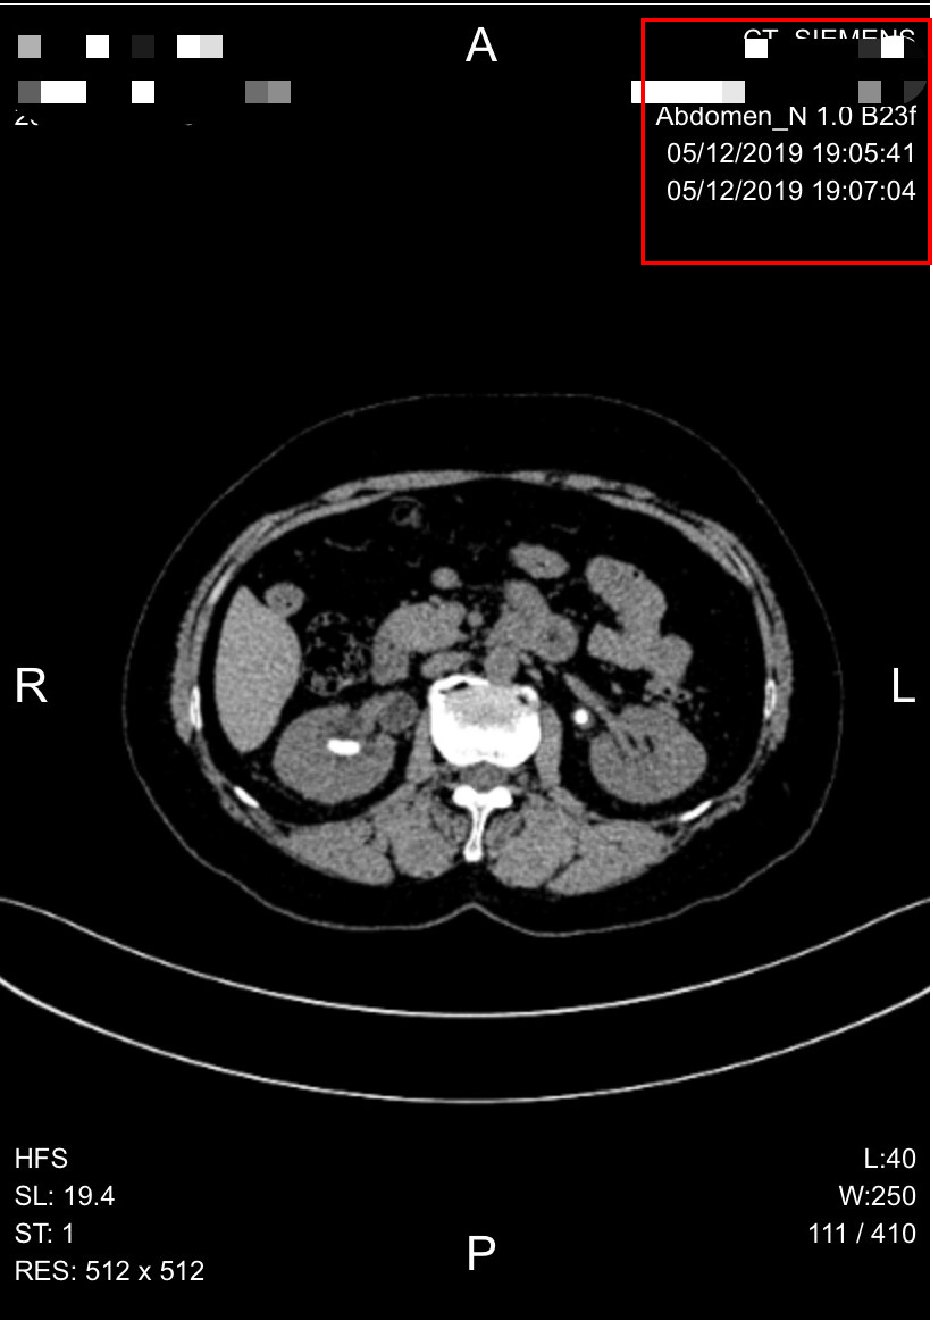

2.把CT片子摆成正确的方向。仔细看看CT片子上的英文字母或者汉字,把字母或者汉字的方向摆正了,CT片子的方向就正确了。我经常收到方向千奇百怪的CT图像,上下颠倒,左右颠倒,甚至正反颠倒,根本不能阅片。按照下面的方向摆,就对了。

3.把手机横过来,给CT片子按照从上到下,从左到右的顺序拍照。一张CT片子,最好分成六次拍照。左上,右上,左中,右中,左下,右下。大部分患者拍照,都是一张CT片子只拍一张照片就传过来了,这样根本看不清楚。排成下图这样的清晰度最好。四个格格一张图,最清楚。